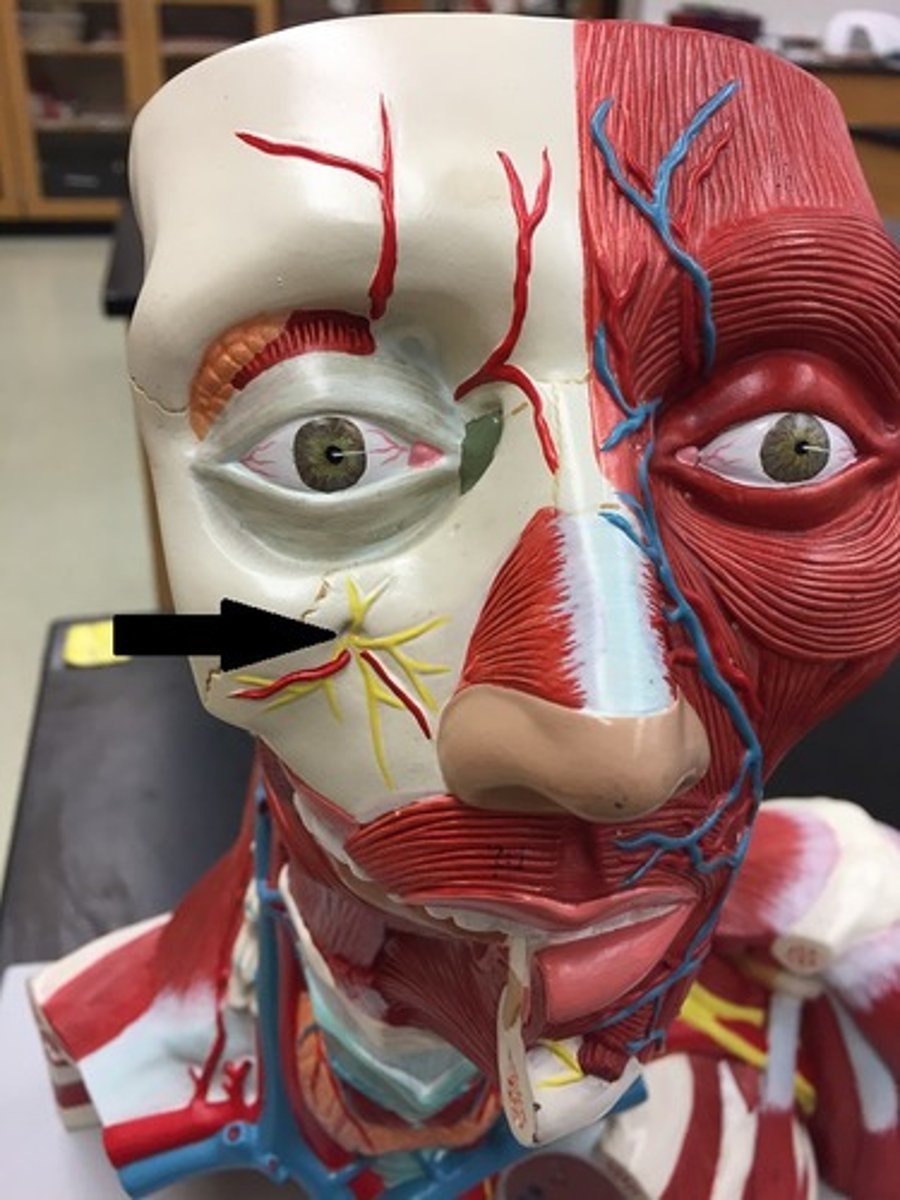

trigeminal nerve

facial nerve

infraorbital nerve

maxillary nerve (V2)

Buccal nerve